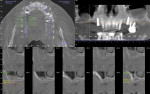

A 49-year-old nonsmoking male presented for treatment of his advanced tooth loss, terminal dentition, residual infection after dental treatment, and recurrent sinus infections. His dental history consisted of multiple attempts at conventional treatment approaches to prolong tooth longevity, several implant procedures to replace failing endodontically treated teeth and edentulous sites (all resulting in repeated failure of treatment), compromised esthetics, and various secondary infectious diseases related to previous failures of dental treatment. The pretreatment CT scan view of the maxillae and several serial views (Figure 20) demonstrated multiple edentulous sites, residual sinus infections, failing implant procedures with large alveolar defects, and the remaining dentition, which can be classified as a “terminal dentition.” After reviewing multiple treatment options with the patient ranging from conventional fixed and removable options, to partial implant reconstruction with extensive bone replacement procedures recommended, the patient opted for removal of most of the remaining dentition, correction of sinus pathology, multiple implant placement, and immediate provisionalization procedures, most accomplished by a conservative, minimally invasive protocol (except for the sinus regions, which required flap access and a lateral-wall osteotomy), and immediate loading of the implants at the initial and only surgical procedure planned. After extensive medical and dental histories were taken, medical clearance for the preexisting sinus infections was obtained, and a complete dental workup consisting of a facebow transfer, mounted maxillary and mandibular pretreatment models, a complete diagnostic waxup of both the hard and soft tissues required to be replaced, and construction of the TempStent II surgical guide and provisionalization system, the patient was given an appointment for the complex surgical visit. During this surgery, remaining dentition and implants were removed, ten implants in the maxillary arch were inserted, and bilateral sinus elevations and alveolar reconstruction was performed along with peri-implant bone grafting and immediate provisionalization. In the mandibular arch, removal of the remaining dentition was done, except for teeth Nos. 21, 22, 27, and 28, and six implants were placed and immediately provisionalized, keeping the patient in the planned first-molar occlusion scheme. The immediate post-treatment panoramic view can be seen in Figure 21. After an uneventful healing for 4.5 months, the patient then initiated the final reconstructive phase of his treatment. A 7-year post-treatment clinical view can be seen in Figure 22, with the 7-year post-treatment CT panoramic scan, axial and serial views of the maxillary central incisor seen in Figure 23.